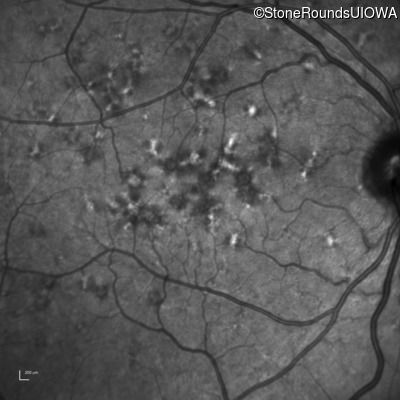

Blue Autofluorescence - Left - 20/32 sc

Exemplar